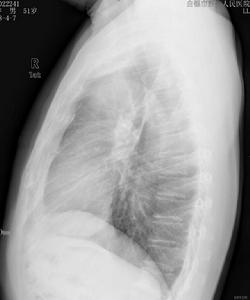

胸部病變與其他系統疾病一樣,周密詳細的病史和體格檢查是診斷呼吸系疾病的基礎,X線胸部檢查對肺部病變具有特殊的的重要作用。由於呼吸系疾病常為全身性疾病的一種表現,還應結合常規化驗及其他特殊檢查結果,進行全面綜合分析,力求作出病因、解剖、病理和功能的診斷。呼吸系統的咳嗽、咳痰、咯血、氣急、哮鳴、胸痛等症狀,雖為一般肺部所共有,但仍各有一定的特點,可能為診斷提供參考。